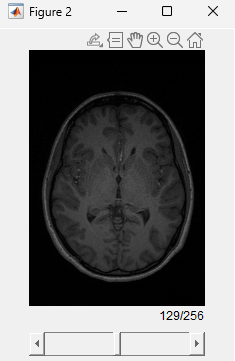

Visualize the anatomical MRI volume.

figure sliceViewer(anatMRI)